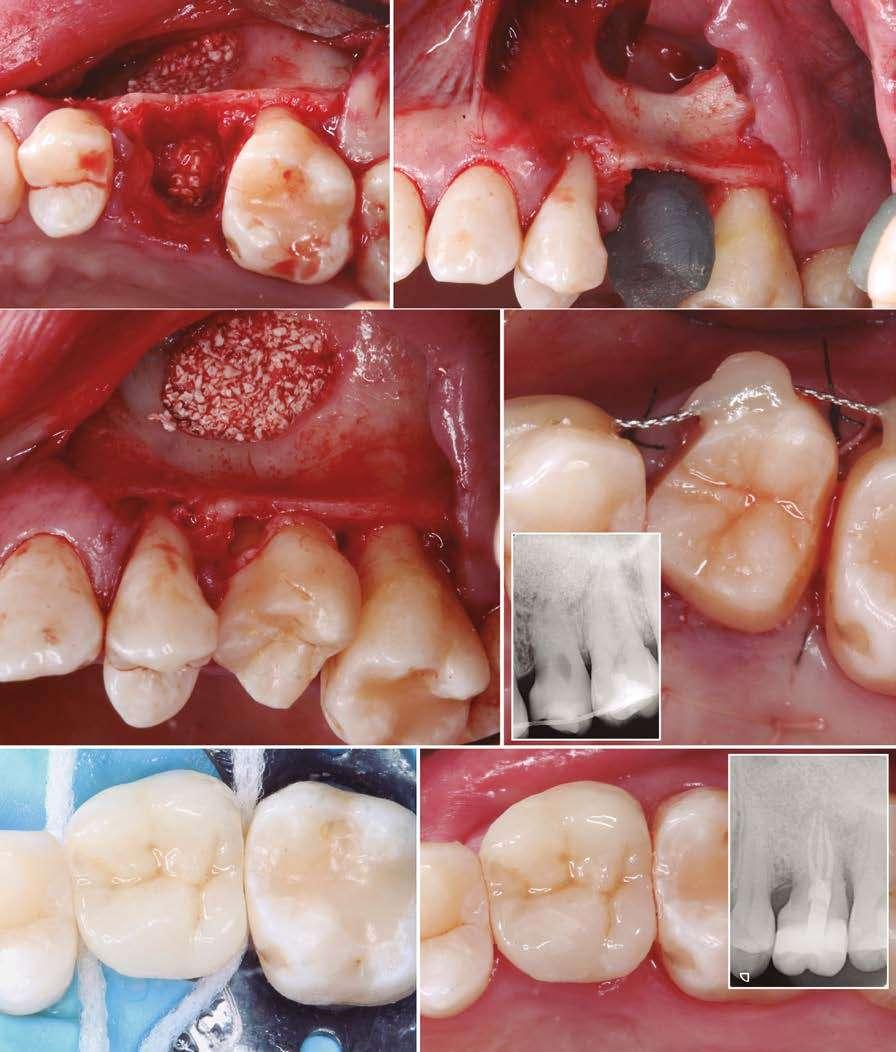

Figuras 3 y 4 . Corte del Cone-beam dental tras la exodoncia y regeneración del alveolo con Endoret-PRGF cuatro semanas después. Podemos observar la atrofia ósea en sentido vertical de la zona con una altura máxima de 3 mm. La planificación como podemos visualizar será para la realización de una elevación transcrestal mínima y la colocación de un implante extracorto.

Figuras 5 y 6. Inicio de fresado de la cortical inferior del seno maxilar con la fresa de corte frontal.

Figuras 7 y 8. Despegamiento de la membrana para comenzar la elevación transcrestal.

Figuras 9 y 10. Inserción de membrana de fibrina como material de relleno en el neo-alveolo y colocación del implante.

Figura 11. Colocación de la corona con el transepitelial unitario 6 meses tras la cirugía.

Figura 12. Mantenimiento de la altura ósea lograda y de la estabilidad del implante al año de carga visualizada en cone-beam.

Figura 13. Estabilidad del tratamiento a los 7 años. No existe pérdida ósea asociada ni problemas relacionados con la prótesis.